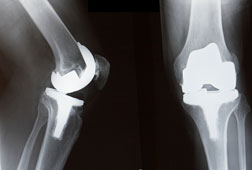

Knee revisions are typically done years – even a decade or more later – due to parts coming loose, wear and tear or instability. The operation replaces the damaged part or the entire implant. Why yours failed so soon is not clear.

During a knee replacement, joints are cemented into position or in some cases, bone is expected to grow into the surface of the implant. Either way, the implant was fixed to the bone. A knee revision is complex surgery and what you really need to do is ensure you have an expert in revision surgery as you need the best outcome possible.